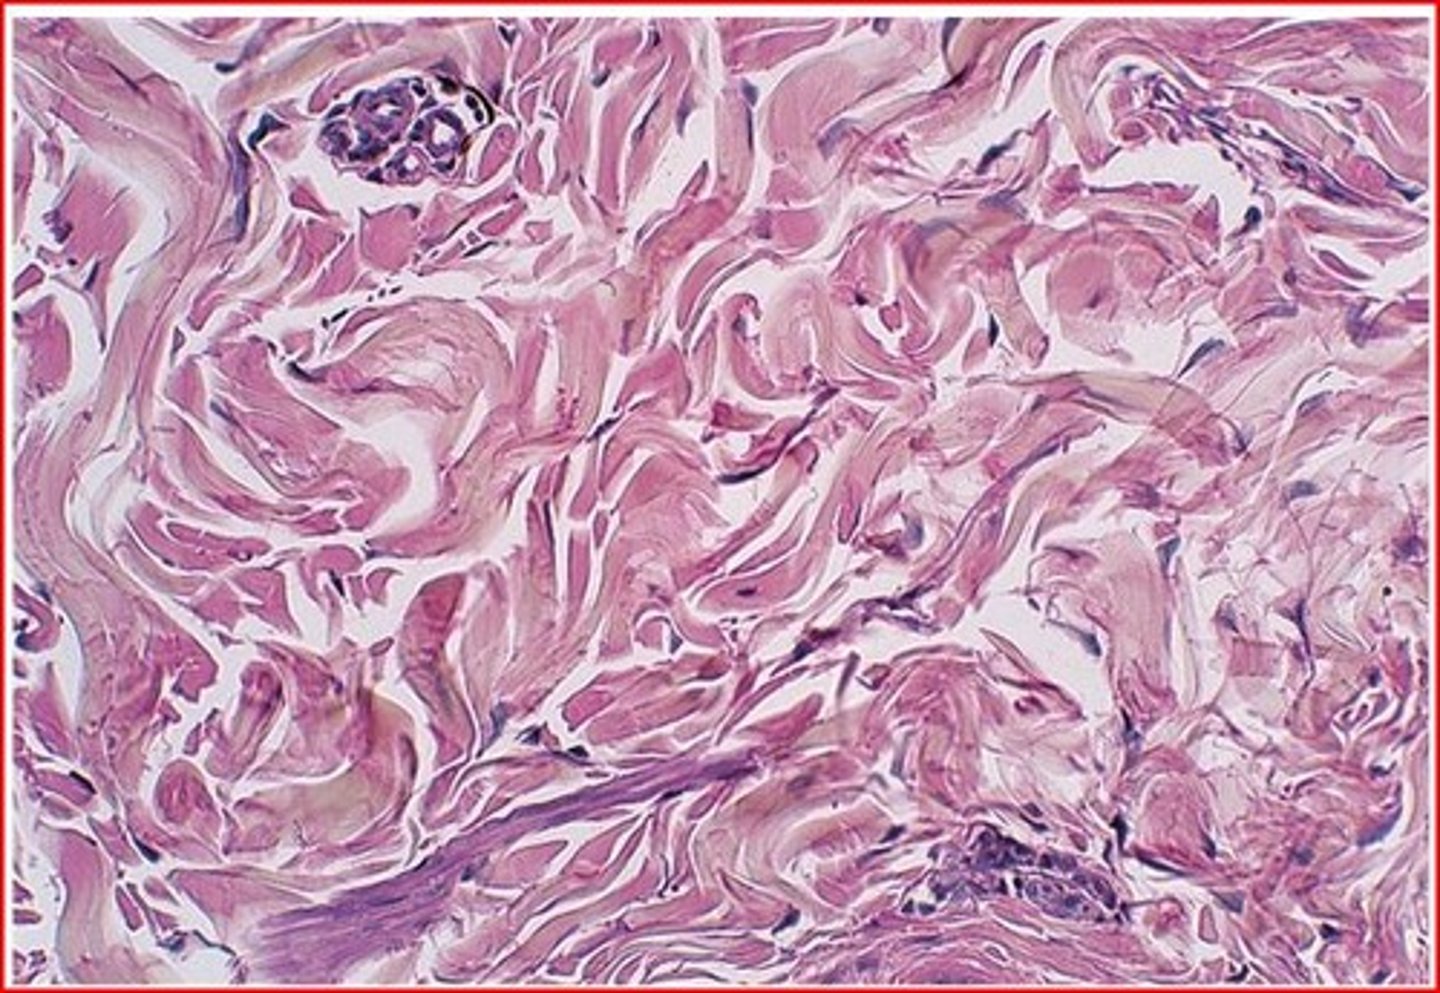

Dense Regular CT

Parallel collagen fibers; few elastic fibers; Cells: Fibroblasts; Function: Strong attachment (tensile strength one direction); Location: Tendons, ligaments.

Dense Irregular CT

Irregularly arranged collagen bundles; Cells: Fibroblasts; Function: Strength in multiple directions; Location: Dermis of skin, joint capsules.